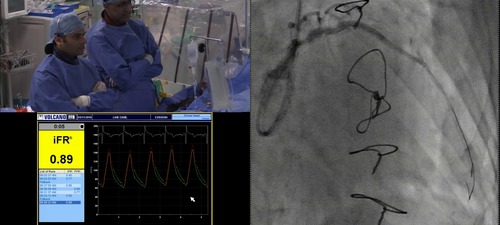

iFR measurement was repeated by the live case operator following PCI to the left anterior descending artery

iFR measurement was made following PCI